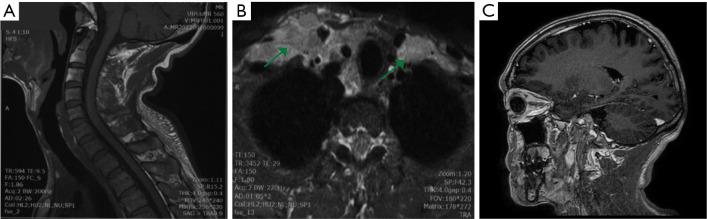

We present a 54-year-old man with SMARCB1/INI1-deficient lung cancer, pathologically confirmed by computed tomography guided percutaneous pulmonary mass biopsy and ultrasound-guided lymph node biopsy. Both lymphoids and lung tissues showed INI1 deletion and high Ki-67 index; next generation sequencing (NGS) indicated a tumor protein 53 () mutation abundance of 22.18% and cyclin-dependent kinase 4 () amplification (copy number of 4.30). Currently, SMARCB1/INI1-deficient lung cancer is rare, and no standardized treatment plan is available, and there was no clear and effective targeted drug. Considering the high expression of programmed cell death ligand 1 (PD-L1), the patient was advised to undergo treatment with anti-programmed cell death 1 (PD-1) immune checkpoint inhibitors. Unfortunately, because the patient and his family have low financial resources, only afford resident insurance and cannot afford follow-up medical expenses, the patient refused treatment and passed away 3 months after diagnosis.

We provided the clinical symptoms, imaging data, and literature findings of this rare case of SMARCB1/INI1-deficient lung cancer with lymph node metastasis as a reference, hoping to help clinicians and pathologists have a better understanding of it and avoid misdiagnosis.